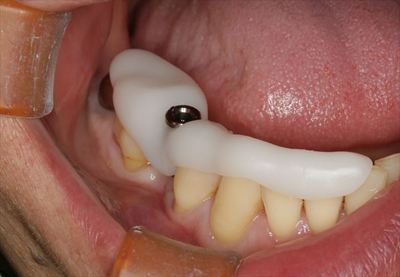

無事に埋入を終えました。

骨吸収を防ぐため、デコルチケーション後にハイドロキシアパタイトを填入します。

減張切開後に縫合封鎖しました。